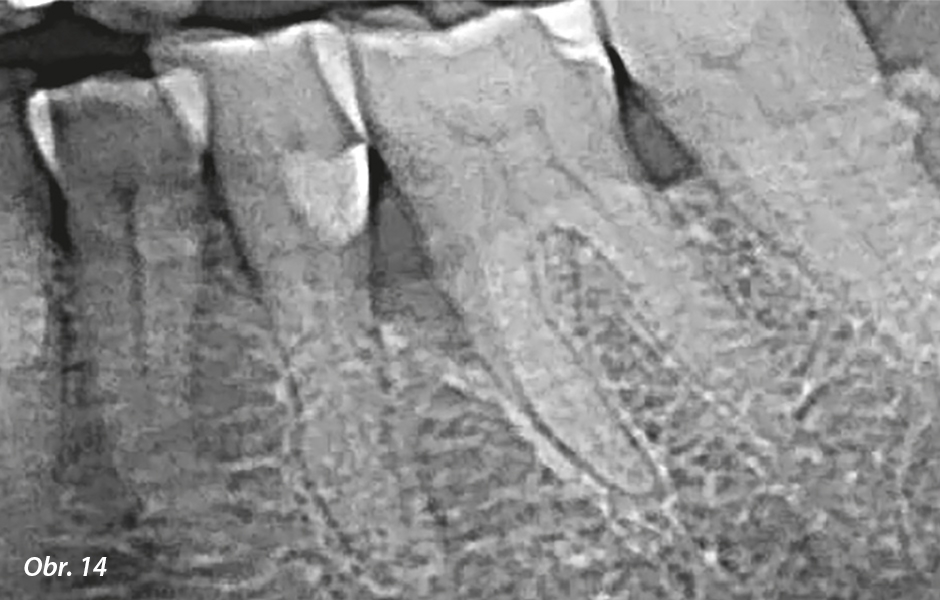

60letá žena trpěla těžkou parodontitidou a bohužel jsme museli extrahovat moláry a premoláry s mobilitou třetího stupně a hnisavou exsudací z chobotů. Levý dolní molárový kvadrant nicméně mohl být připraven na otevřený lalokový debridement za použití glycinového prášku při doplňkovém pískování. Před chirurgickým zákrokem byl zjištěn v mezioaproximální oblasti levého dolního prvního moláru třístěnný vertikální kostní defekt s průměrnou hloubkou 8 mm. Po zlepšení orální hygieny jsme přistoupili k otevřené lalokové operaci. Povrch kořene v kostním defektu jsme ošetřili pískovačem. Z důvodu dokonalého zhojení a řádné regenerace defektu jsme použili protein ze sklovinné matrix (Emdogain®, Straumann).12

Průměrné parametry před chirurgickým zákrokem (obr. 13–15): PPD (mm): 5,5 | GR (mm): 2,3 | BoP (%): 66 | PI (%): 50| CAL: 7,8

Počáteční RTG snímek